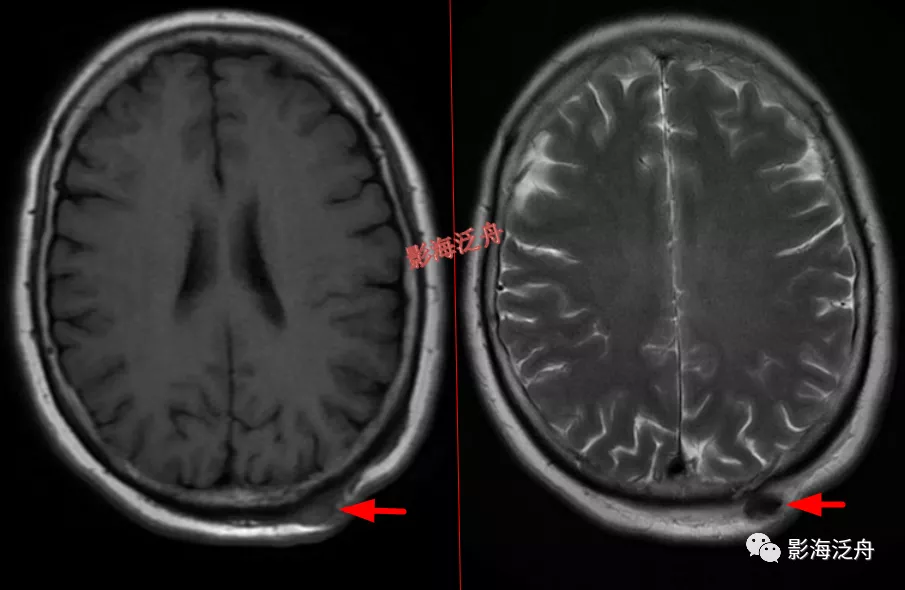

头皮血肿(急性期),病灶在T1WI及T2WI上均呈低信号。